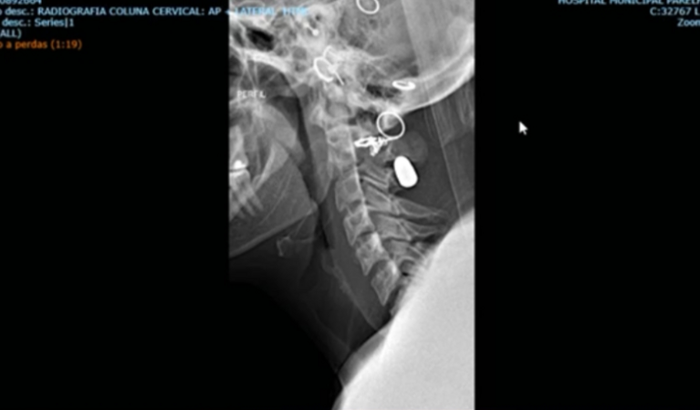

No dia 12/01/2023 era uma quinta feira , sai com umas amigas para happy hour em um espetinho na cidade de Embu Guaçu e por voltas da 23 hs ocorreu um tiroteio no local, onde eu fui atingida por uma bala perdida, que entrou pela minha nuca e ficou alojada na musculatura paravertebral direita ao nível do corpo vertebral da C4( pescoço), consegui o cirurgião mas preciso pagar os custos hospitalares. ****Cirurgia agendada para 14/04 ( disponibilidade do médico). *****